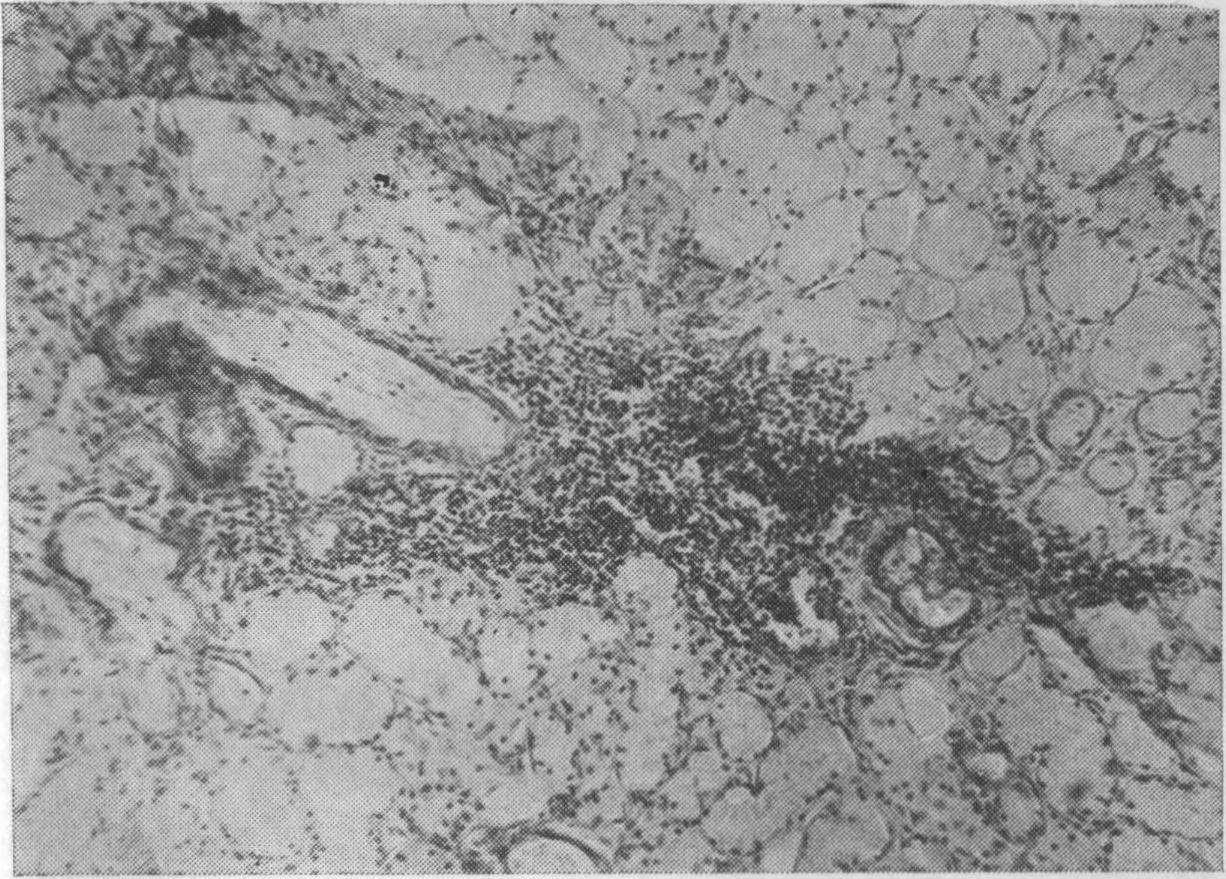

Рис. 38. Слизистые железы задней трети твердого неба женщины 53 лет, пользовавшейся протезом 6 лет. Круглоклеточная инфильтрация стромы. Окраска пикрофуксином. Х80 (Дуйшалнев К. Д.).

Обширные инфильтрированные участки желез замещались жировой и соединительной тканью (рис. 39), что подтверждает данные Р. Ш. Шаймерденовой (1969), Н. Zander (1960). По сравнению с контрольной группой имело место некоторое увеличение клеток жировой ткани в подслизистой основе и разрастание соединительной ткани в междольковых прослойках. Увеличение жировой и соединительной ткани, по-видимому, не только

Рис. 46. Кость альвеолярного отростка. Мужчина 77 лет, срок пользования протезом 3 года, а — лакунарное рассасывание кости альвеолярного отростка со скоплением остеокластов. Окраска гематоксилин-эозином. Х400; б — резорбция костной балки остеокластами (1). Слева в углу полости (2) располагается остоидная зона, по краям которой расположены остеобласты. На месте исчезнувшей кости — соединительная ткань. Женщина 67 лет, срок пользования протезом 3 года. Окраска гематоксилин-эозином. Х80 (Дуйшалиев К. Д.)-